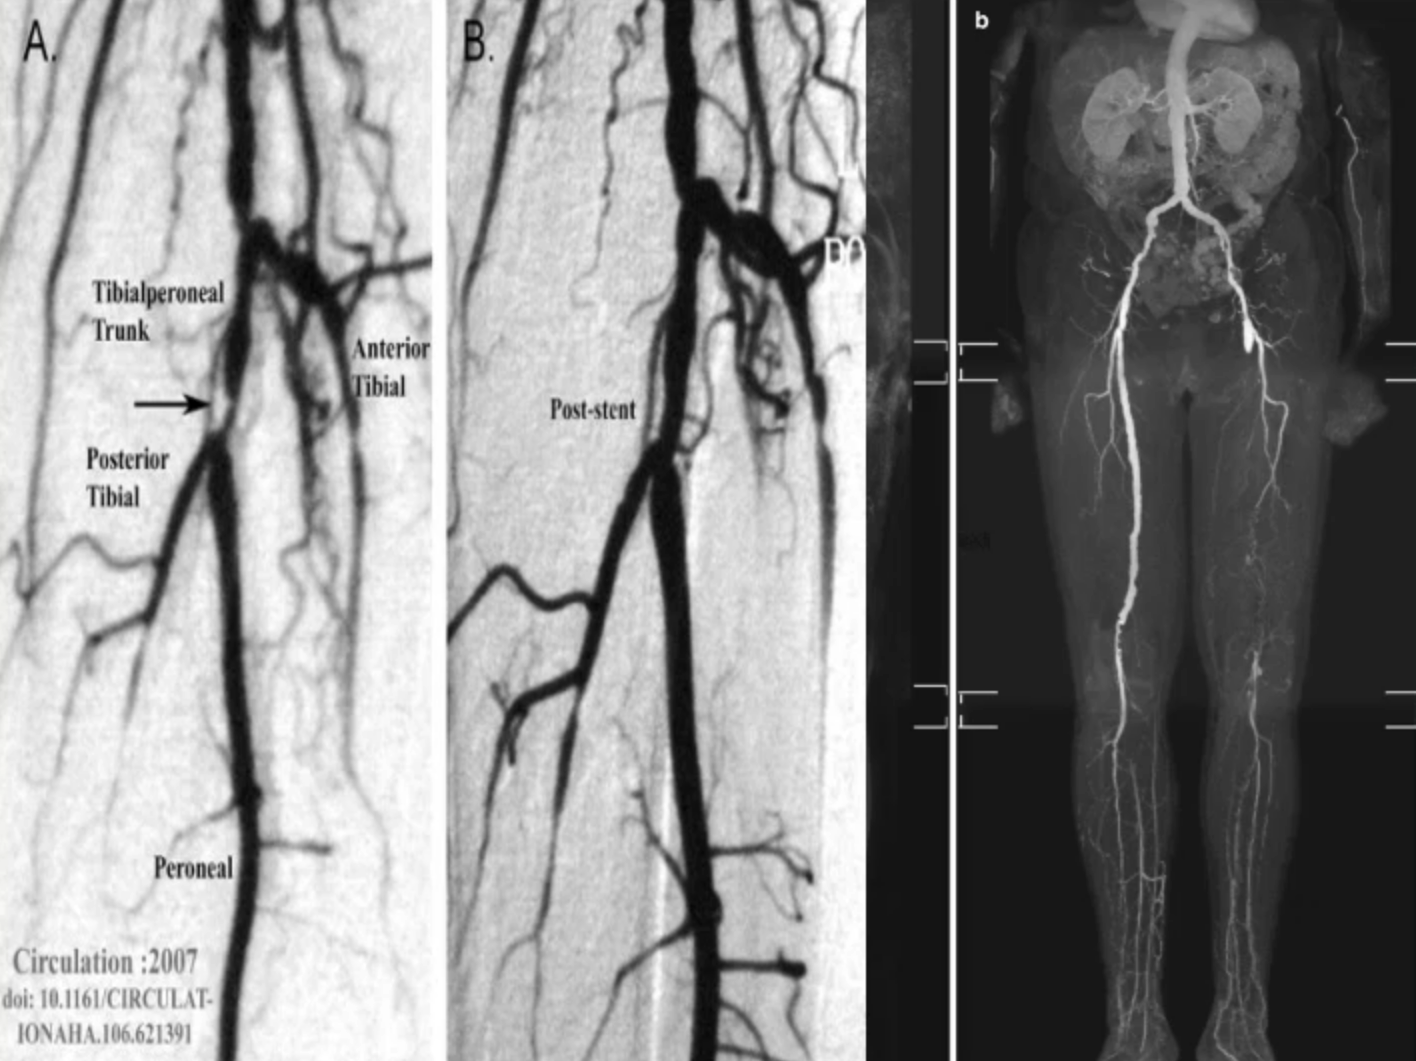

• angiogram (CAT, MRI or xray)

• How severity of PAD can be measured - angiogram (CAT, MRI or xray)